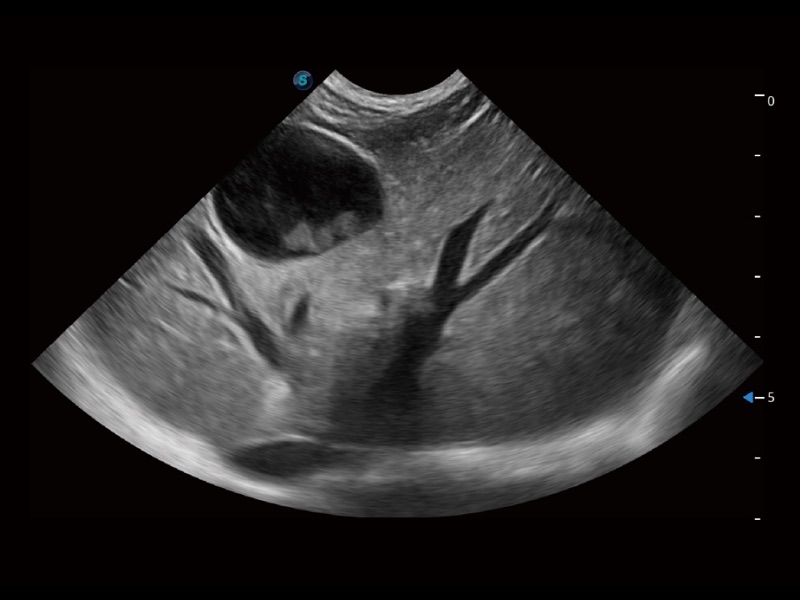

通过创新的 Matrix E自适应滤波器和超长时间域算法,极大提升超低速微细血流的检出能力,同时更精准地滤除软组织和噪声信号,为兽用医生提供以往无法通过常规血流获得的疾病诊断信息。

通过色彩血流和实时宽景相结合,可观察到完整的静脉或动脉的血流,方便医生检查。实时扫查过程中,如有任何操作失误也可以很容易地进行回扫擦除,而不会中断扫查。

提供差异化的图像风格,使动物医生识别疑似病灶更容易,助力医生筛查不漏诊。